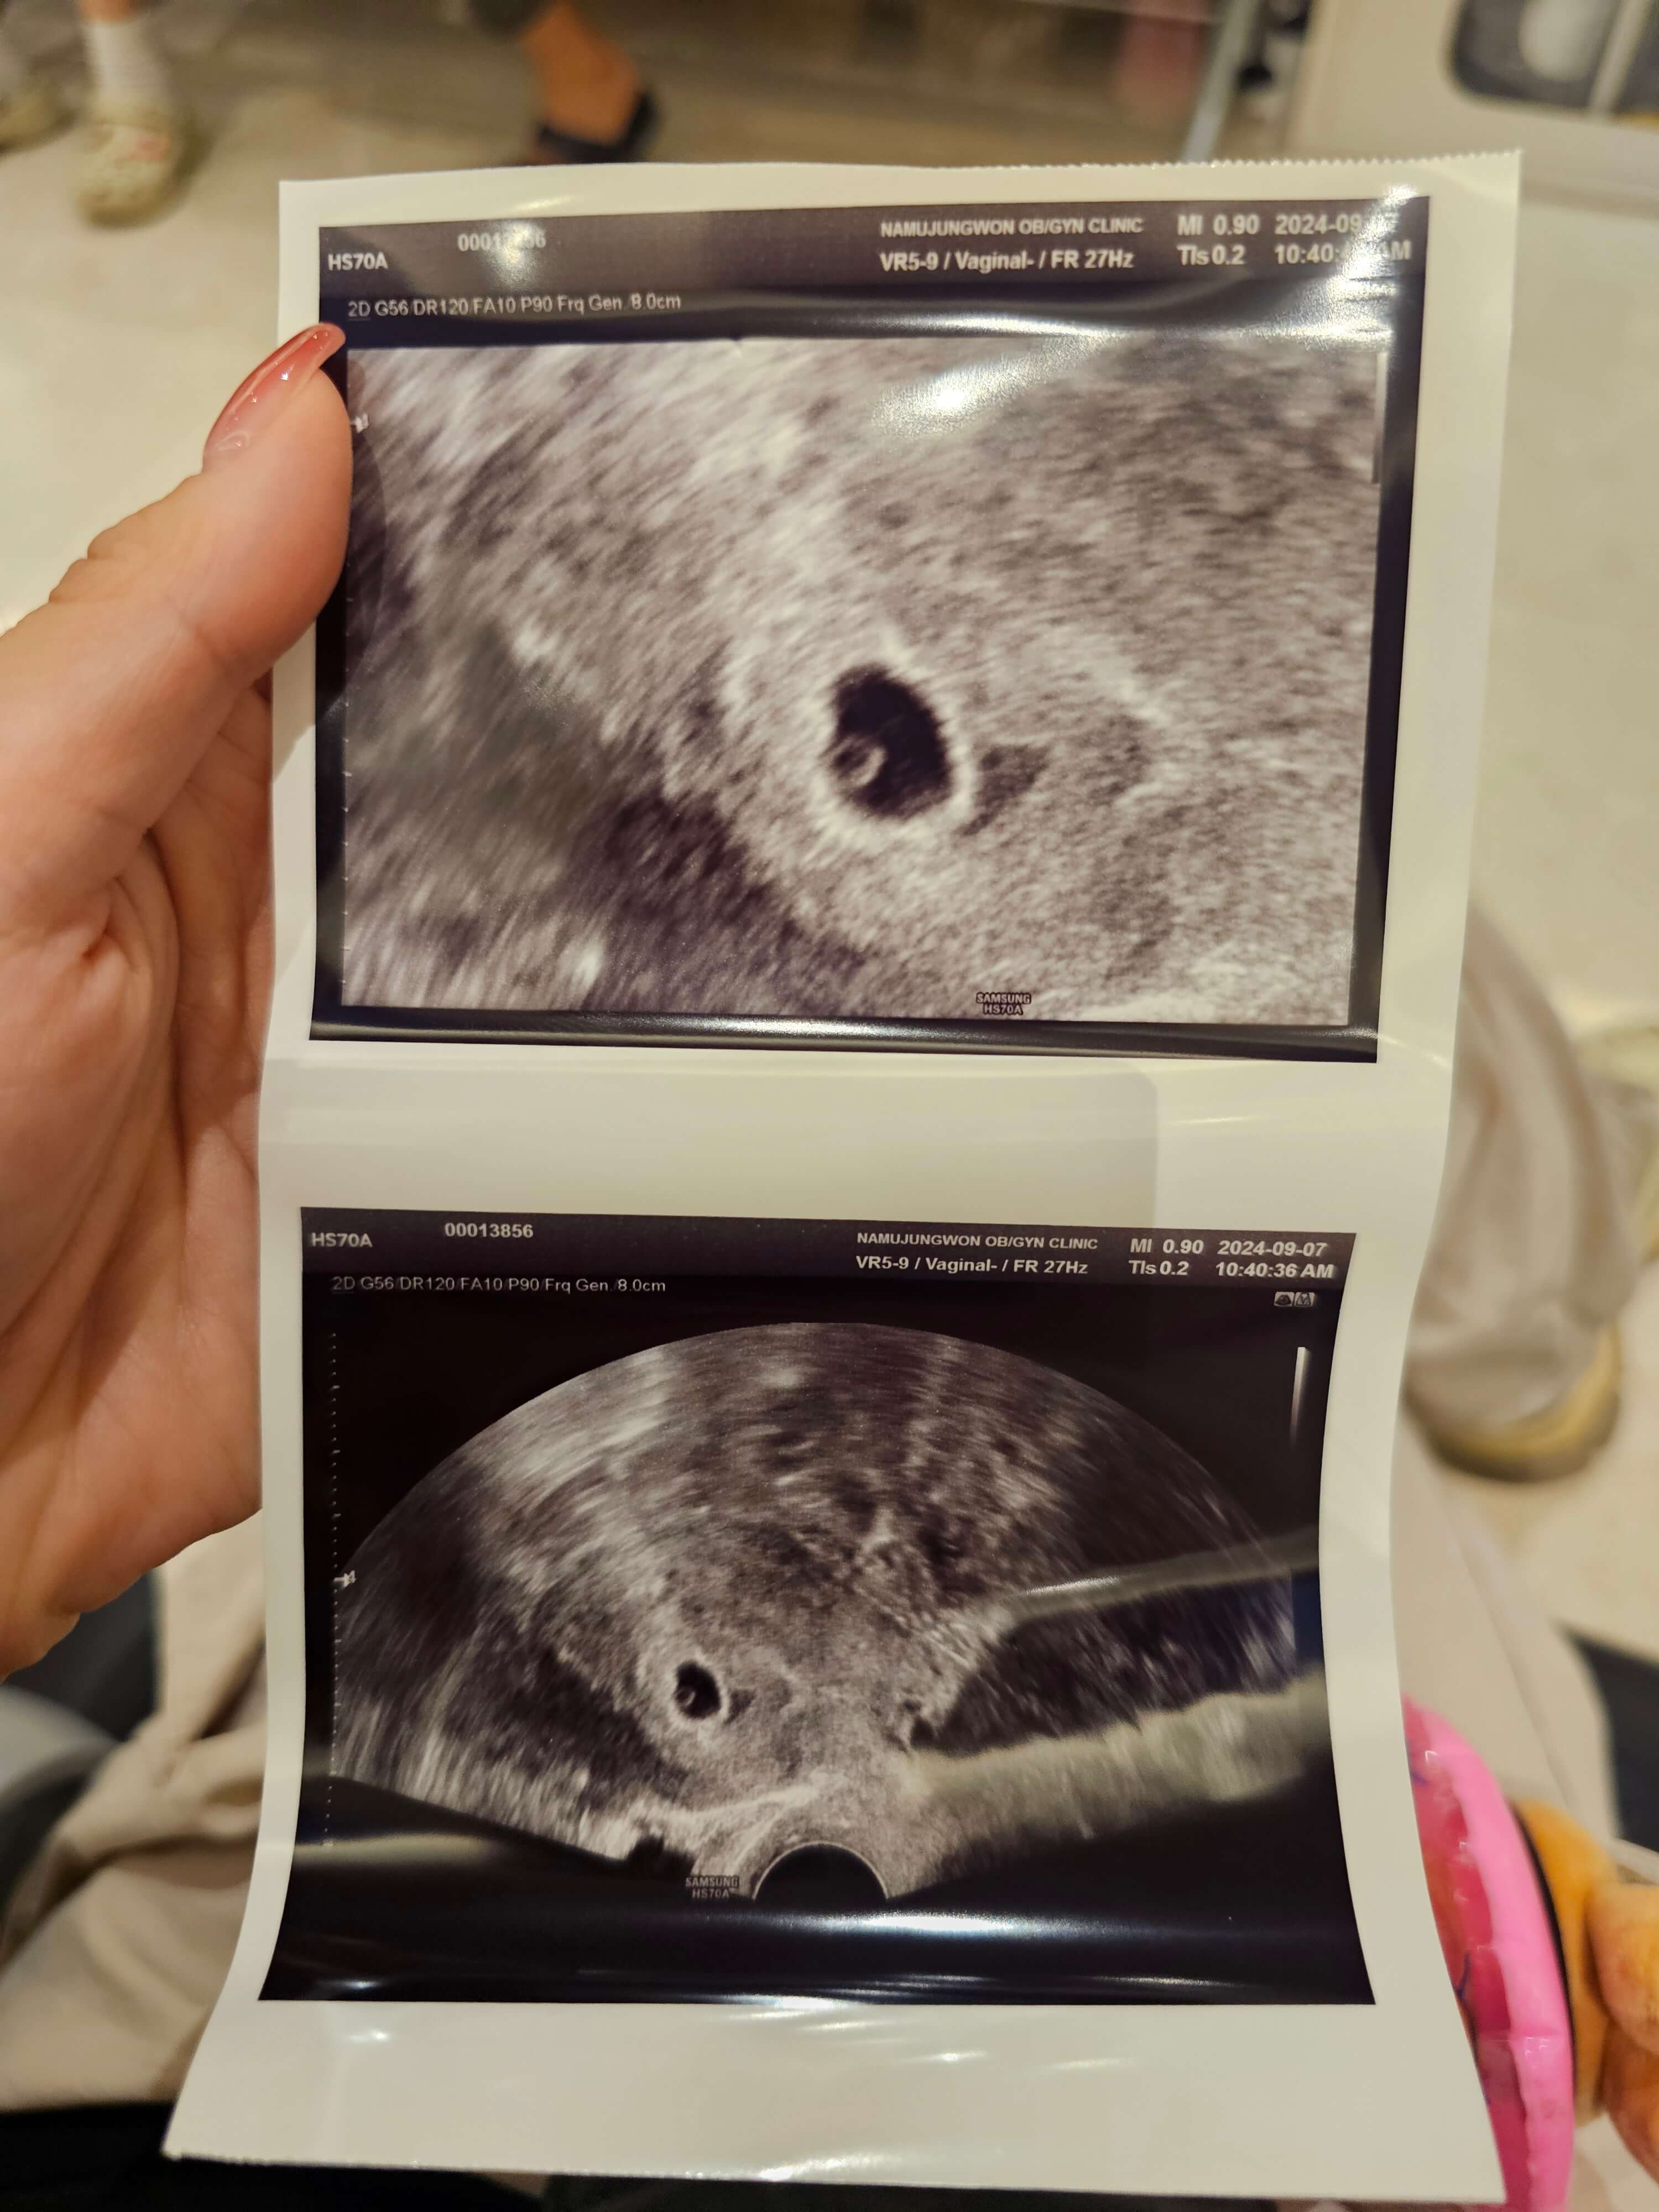

4. 임신 5주차 아기집 확인 및 임신확인서

아기집-확인-임신확인서 쓰리라인 임테기의 1번선이 조금 뚜렸해졌을때, 저는 산부인과를 방문했습니다. 산부인과에 방문하니, 4주 6일 정도로 예상된다고 하셨습니다. 딱, 비슷하게 5주차가 되는 날이었고 조그마한 난황도 확인할 수 있었습니다. 제가 방문했던 산부인과에서는 이렇게 아기집이 확인되면 임신확인서를 주세요. 임신확인서로 이제 바우처도 만들고 모성보호시간으로 단축근무도 가능하답니다!